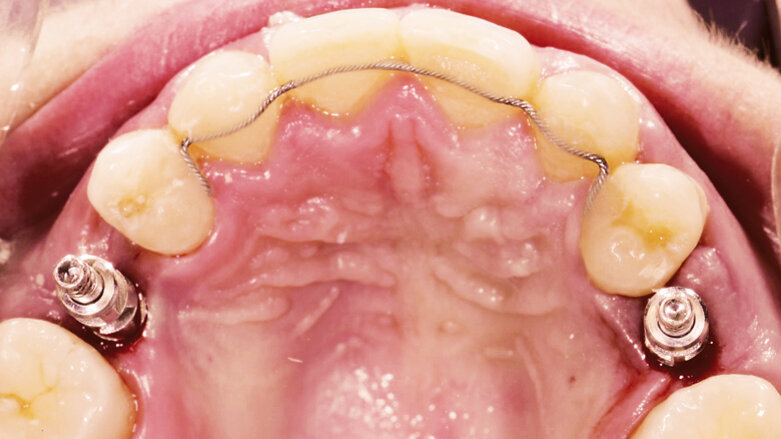

Pacientkou byla jednadvacetiletá žena, která se do zubní ordinace dostavila za účelem náhrady obou horních druhých premolárů, oblast 15 a 25. Pacientka byla v dobrém celkovém zdravotním stavu a nekuřačka. Dříve byla léčena na ortodontickém oddělení Univerzitní nemocnice v Gentu pro mnohočetné ageneze zubů. Intraorální vyšetření ukázalo nepřítomnost obou postranních řezáků a druhých premolárů v horní čelisti a obou druhých premolárů v dolní čelisti. Parodontologické vyšetření neprokázalo žádné známky patologie. Minišrouby pro skeletální kotvení během ortodontické léčby byly stále přítomny ve druhém a čtvrtém kvadrantu. Léčba vyžadovala zavedení dvou zubních implantátů v bezzubých oblastech horní čelisti. Oba implantáty měly být opatřeny provizorními korunkami během dvanácti hodin od zavedení implantátu (okamžité zatížení).

Před zákrokem byl sejmut otisk zubního oblouku pomocí ireverzibilního hydrokoloidu (Cavex CA37, fast set, CavexHolland) pro výrobu studijního modelu. Tento model byl použit pro výrobu chirurgické dlahy, dále jen NaviStent (obr. 1a, b). NaviStent sloužila jako skenovací šablona a byla také použita v průběhu chirurgického zákroku. Poté byla pacientka odeslána s nasazenou NaviStent na vyšetření CBCT (obr. 2; 3a, b; 4a, b).